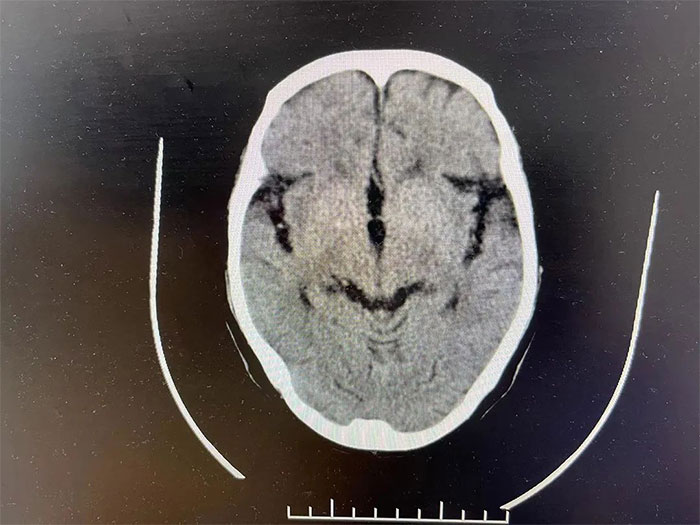

家人聽到動靜趕過來,把吳阿姨小心扶上床后,當(dāng)即撥打了“120”急救電話,火急火燎地就近送往醫(yī)院。入院查體顯示,吳阿姨血壓高達(dá)170/150毫米汞柱,遠(yuǎn)高于正常值。急行頭顱CT檢查,提示右側(cè)大腦頂葉出血(急性期),建議住院進(jìn)行保守治療。